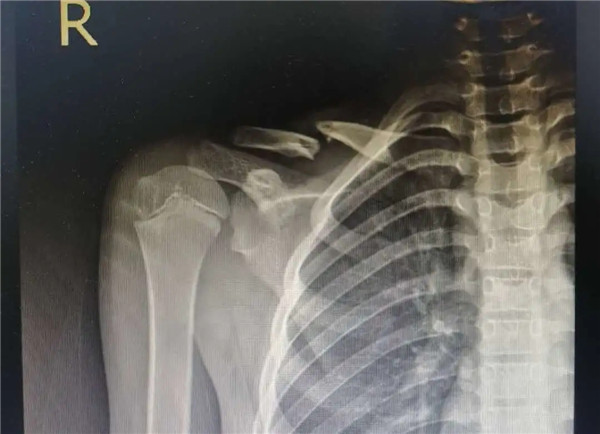

復(fù)位前

經(jīng)拍片顯示,洋洋右鎖骨中遠(yuǎn)段骨折。查體時,洋洋右肩部腫脹,有壓痛感,右肩關(guān)節(jié)上舉、外展活動受限,建議其入院并接受手術(shù)治療。洋洋媽媽當(dāng)即辦理了入院手續(xù)。